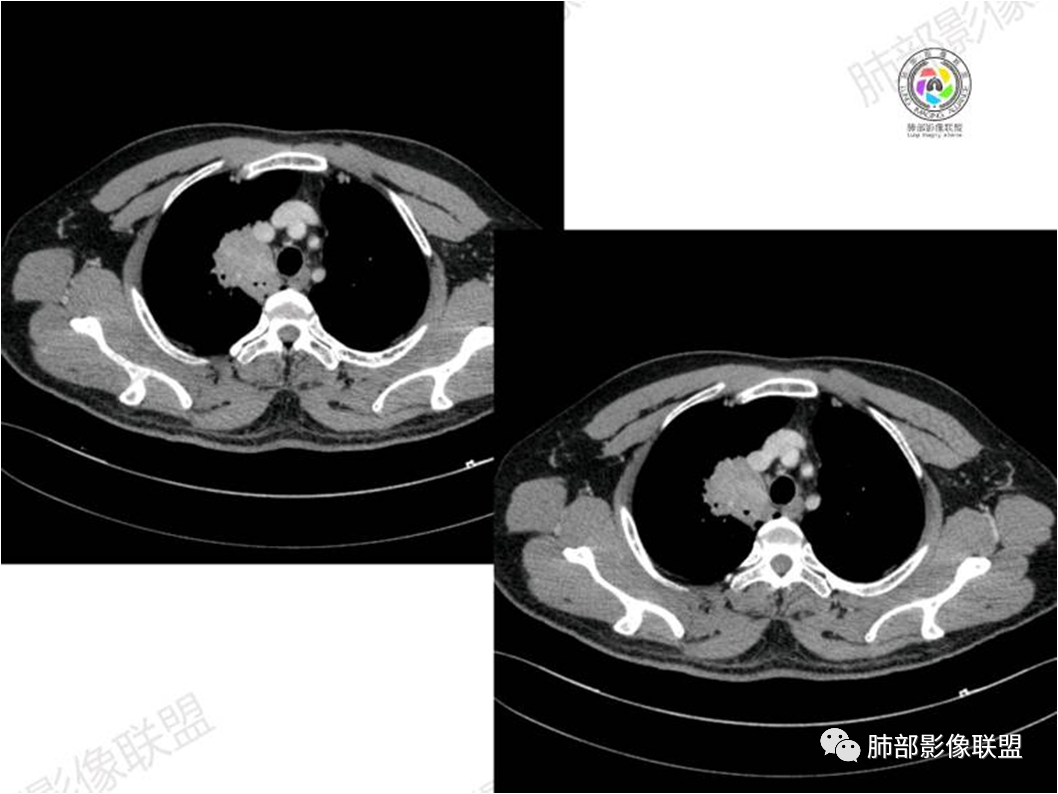

胸部CT:

中年男性,偶有咳嗽,右肺上叶近纵膈旁占位,内可见僵硬的支气管和小空泡征,病灶边缘可见分叶,毛刺,增强病灶中度以上不均匀强化,可见血管造影征,考虑恶性病变,腺癌可能性大。

中年男性,右肺上叶尖段团片病灶,密度均匀,内部支气管充气相,渐进狭窄,强化均匀,血管造影,纵隔侧未见侵犯,诊断:良性,慢性非特异性炎症/机化性炎症,IMT

右肺上叶纵隔胸膜侧一实性肿块,与纵隔胸膜宽基底相连,局部脂肪间隙消失,形态欠规则,内部可见多个小空泡,平扫密度尚均匀,增强后可见点条状强化,内部穿行血管,周围肺组织干净,纵隔淋巴结略肿大,男性44岁,只有咳嗽,考虑恶性肿瘤,腺癌,鳞癌。鉴别结核,OP,炎性假瘤。

右肺上叶近纵膈旁肿块,密度均匀,边缘分叶,毛刺,气管受压变窄,不均匀强化,可见血管造影征,考虑淋巴瘤,鉴别炎性假瘤。

中年男性,右肺上叶纵隔旁软组织肿块,边缘膨隆、毛糙,可见多发分叶,支气管穿行,部分截断,增强后密度欠均匀,纵隔内见多发小淋巴结,首先考虑恶性,腺癌,鉴别淋巴瘤

中年男性,右肺上叶纵隔旁肿瘤,稍膨隆,有毛刺,支气管穿行,远端闭塞,强化均匀,血管走行尚可,考虑淋巴瘤可能性大(支气管远端闭塞,不太符合),鉴别腺癌(气管穿行后闭塞,不太符合),op(病灶稍膨隆)

患者中年男性,咳嗽就诊,无其他不适。胸部CT:右肺上叶尖段上纵膈旁肿块,边界清楚,边缘光滑,内见支气管受压变窄,伴阻塞性改变,增强均匀强化,见血管造影征。综合考虑恶性病变,小细胞肺癌或淋巴瘤。气管镜活检应能明确。

中年男性,右肺上叶纵隔旁实性病灶,边缘有彭隆,有平直,有分叶,有尖角,病灶边缘中心可见支气管征,周围少许磨玻璃,边缘模糊,增强后动脉期病灶可见强化血管影,渐进性强化,临近血管界限清晰。考虑炎性病灶,普通炎性肉芽肿?结核?炎性肌纤维母细胞瘤?鉴别腺癌,淋巴瘤